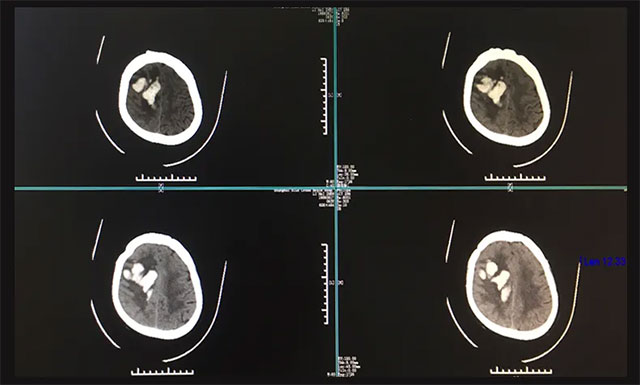

▲ 患者突发脑出血陷入昏迷,情况非常危急

随后,曹先生紧急拨打120电话急救,遂将患者送至当地浙江省某医院进行救治,在该院紧急行头部CT检查,影像提示:患者右侧颞顶叶脑出血,两侧侧脑室后角少量积血。鉴于患者当时出血量很大,约为50ml,病情又比较严重,生命危急,应及早手术,但因各方面条件所限,该医院当时予以保守治疗,并建议患者家属转院。

入院后,完善其各项检查,为了进一步确定患者目前出血的具体情况,进行了头部CT检查,根据影像检查结果,与之前在他院CT结果相比,血肿量较前增多,右侧额颞顶叶出血灶(偏急性期)。经过会诊,潘仁龙主任和吴治群博士一致认为患者脑出血严重,处于昏迷,左侧肢体偏瘫,病情危急,需及早手术清除颅内血肿,否则生命会有危险。